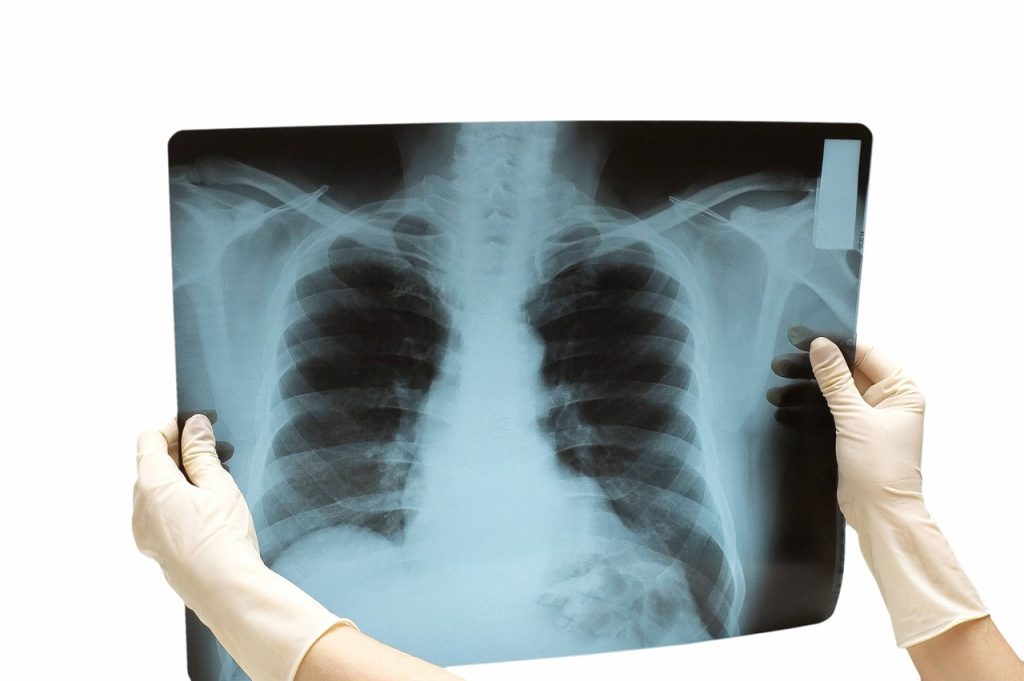

В Узбекистане в тысячи раз быстрее начали диагностировать туберкулез

Раньше на точную диагностику туберкулеза в Узбекистане уходило 3-4 месяца, а теперь точно диагностировать заболевание можно всего за 70 минут (в 2-2,5 тысяч раз быстрее) с помощью геномолекулярного метода (ПЦР).

По Узбекистану действуют 97 ПЦР-лабораторий, 40 из них расположены в учреждениях первичной медико-санитарной помощи.

Для проведения скрининга на туберкулез и респираторные заболевания населения, проживающего в отдаленных районах областей, мобильные бригады «Здоровье легких» были обеспечены микроавтобусами и 4 видами оборудования (мобильный цифровой рентген с искусственным интеллектом). система, ПЦР, электрокардиограф, мобильный спирометр) за счет средств местного бюджета.